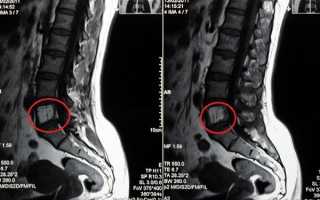

Диагностика заболевания

На начальных этапах заболевания симптомы могут быть слабо выражены, поэтому его, как правило, выявляют случайно во время обследования по другим причинам, связанным с опорно-двигательным аппаратом.

Если у человека появляются боли в спине, которые ранее не беспокоили, ему настоятельно рекомендуется незамедлительно обратиться к неврологу, ортопеду или хирургу для проведения обследования.

Диагностика осуществляется под наблюдением специалистов с использованием компьютерной томографии, магнитно-резонансной томографии и рентгенографии. В случае подозрения на гемангиому позвоночника, лечащий врач, совместно с вертебрологом и нейрохирургом, принимает решение о необходимости хирургического вмешательства.